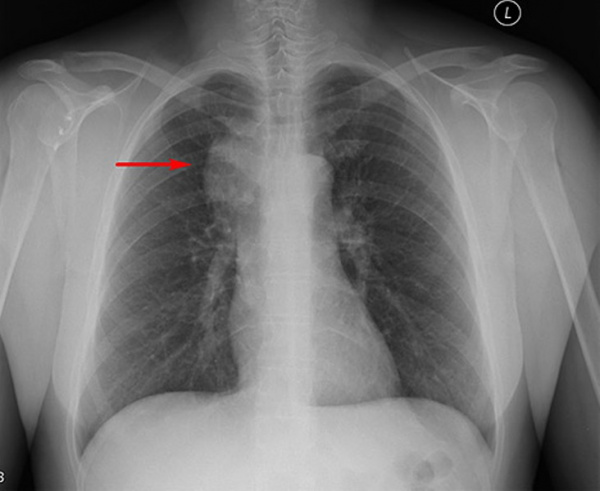

• Рентгенография органов грудной клетки:

о Плевральный выпот, высокое стояние диафрагмы, кардиомегалия (23%)

(Слева) МРТ, сагиттальная проекция, режим STIR: у пациента с подтвержденной плазмоклеточной пролиферацией визуализируются множественные низкоинтенсивные очаги. Некоторые из них окружены зоной высокоинтенсивного сигнала. Обычные активные миеломные (не POEMS) очаги характеризовались бы полной гиперинтенсивностью.

(Справа) МРТ, корональная проекция, режим STIR: у этого же пациента визуализируется множественное поражение грудины в виде низкоинтенсивных очагов. В режиме Т1 они характеризовались аналогичным сигналом низкой интенсивности. Рентгенографически определялись соответствующие склеротические участки. У пациента имеется склеротическое поражение костей, характерное для POEMS синдрома.